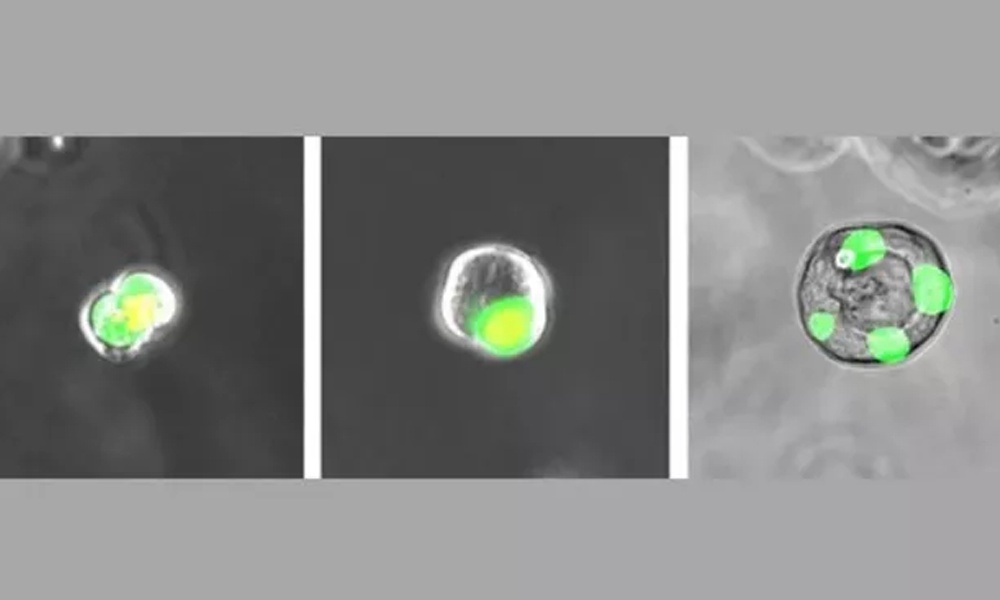

(Imagem: Reproduçãp/University of Pennsylvania)